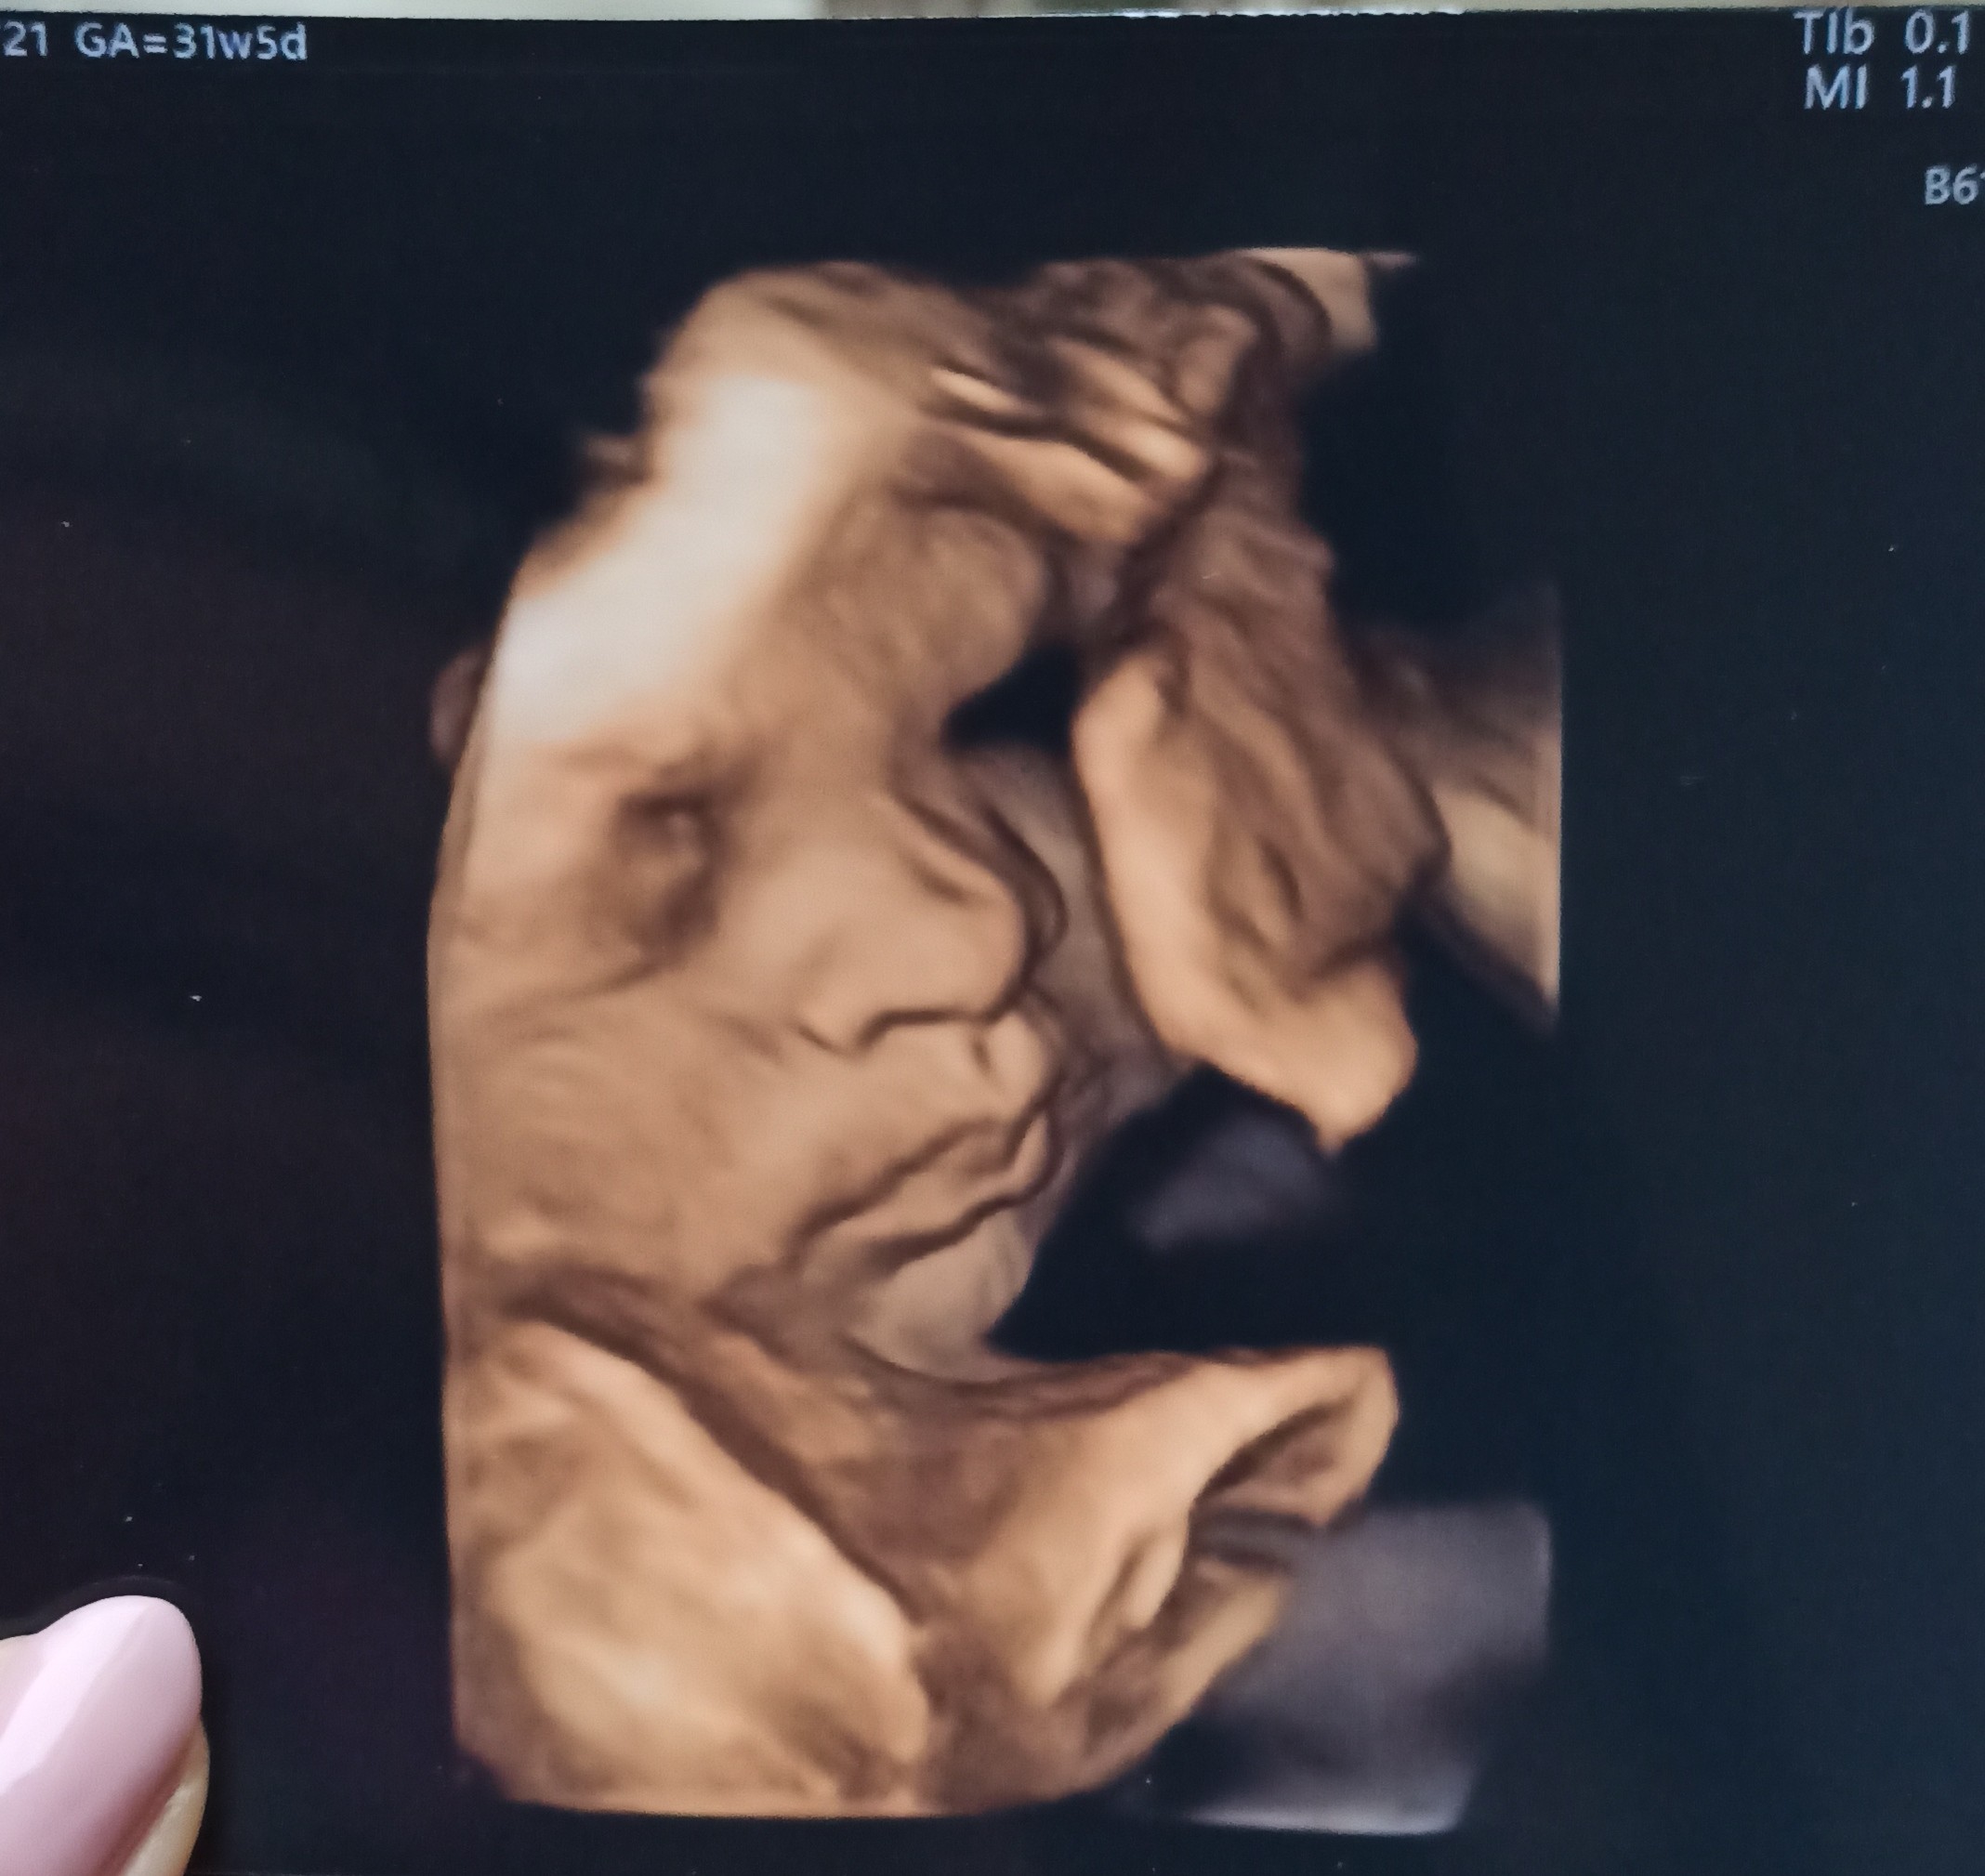

A ja dziewczynki wczoraj miałam wizytę. Było 31+6. Mała wazy 2046 plus minus 298g. Lekarka mówi,że wazy dobrze. Aplikacje mi pokazuje,ze powinna ważyć ok 1800.. i już mi się załączyła myśląca...

Poza tym szyjka mi się skróciła od ostatniej wizyty z 33 do 25mm i powiedziała,że mam więcej leżeć i się oszczędzać. Kolejna wizyta za 3tyg i 3 dni dokładnie. Przez ta szyjke to ja dziś spać nie mogłam. Nawet dłonie mi bardziej dretwialy i bolały w nocy ;/

Królewna spala w najlepszez ale udało się w końcu zrobić fotkę buzi bo najczęściej to zakrywa.

Sprawdziłam i moje baby w 32t2d (obie były tego samego dnia u lekarza [emoji38]) ważyły ok 1900g, to był 48 percentyl i jedna urodzila sie 3090 a druga 3330g, więc Twoja Hania szykuje się większa [emoji4] Przy takiej tendencji będzie pewnie mieć ok 4kg, ale to się jeszcze może zmienić. Na następnym usg już będzie 35t I wtedy łatwiej obliczyć, bo w ostatnich tyg będzie przybierać ok 200-250g tyg więc jeśli wtedy będzie ważyć powiedzmy 2300, to w terminie powinna mieć ok 3700.

Spokojnie, sliczna jest i ładnie rośnie.